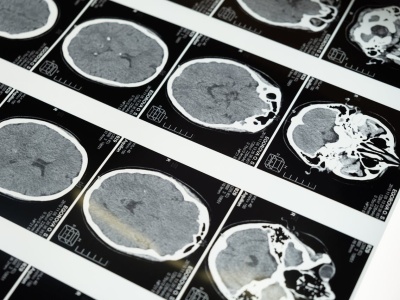

Jeden skan mózgu wystarczy, by określić tempo starzenia się i ryzyko chorób

Upływający czas zmienia nas w różnym tempie, a najbardziej chyba widocznym przypomnieniem tego zjawiska są spotkania klasowe po dekadach. Jedni ich uczestnicy są bardzo sprawni fizycznie i umysłowo, inni zaczynają odczuwać upływ czasu wcześniej. Nauk...

Czy to guz mózgu? Nie ignoruj tych sygnałów

Głowy nie badamy często - musimy mieć faktycznie powody do niepokoju. Przyjęło się, że może czasami boleć i są osoby, które częściej skarżą się na tę dolegliwość. A kiedy warto zadać sobie pytanie, czy to może być guz? Jakie mogą być powody do dalsze...